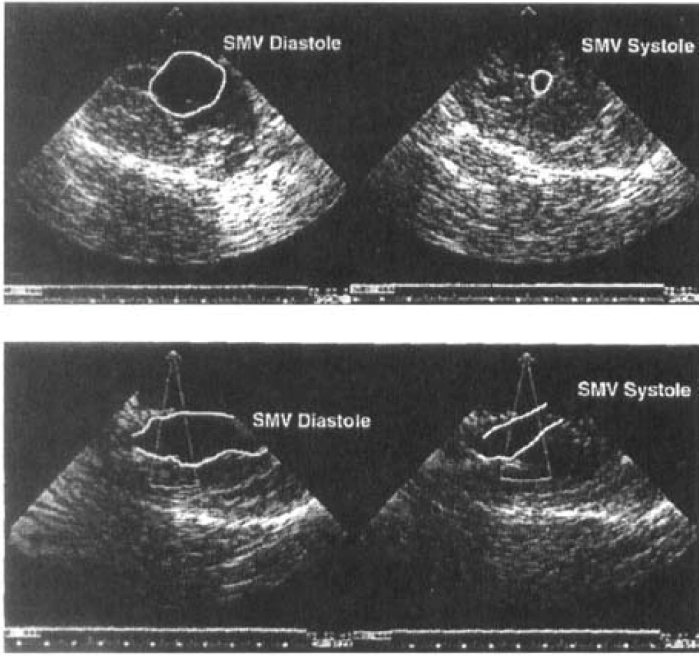

Fig. 2.Echocardiographic examination of the skeletal muscle ventricle (SMV) functioning in continuity with the circulation. Top shows short-axis view, and bottom shows long-axis view. Note vigorous contraction between systole and diastole. Reprinted with permission from Reference [3].